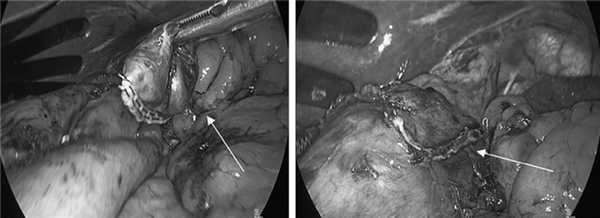

С учетом клинической симптоматики и полученных при обследовании данных решено выполнить иссечение дивертикула желудка лапароскопическим доступом. Под общим обезболиванием после наложения пневмоперитонеума и установки в брюшную полость троакаров при помощи аппарата Ligasure произведена мобилизация дна и кардиального отдела желудка по большой кривизне. Пересечены частично желудочно-ободочная связка, желудочно-селезеночная связка, короткие желудочные сосуды. Выполнена медиальная ротация дна желудка. При помощи интраоперационной эндовидеотрансиллюминации желудка определено, что дивертикул расположен по задней поверхности кардиального отдела желудка ближе к малой кривизне, на 3 см ниже пищеводно-желудочного перехода (рис. 4).

Рис. 4. Мобилизация дивертикула задней стенки кардиального отдела желудка (интраоперационные фотографии).

Из-за явлений перидивертикулита с техническими трудностями выполнена мобилизация дивертикула из рыхлых и плотных его сращений с задней стенкой желудка, после чего дивертикул одномоментно прошит и отсечен у основания сшивающим аппаратом EndoGIA (рис. 5).

Рис. 5. Видеолапароскопическая резекция дивертикула (интраоперационные фотографии).